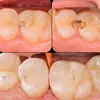

Diş Çürükleri